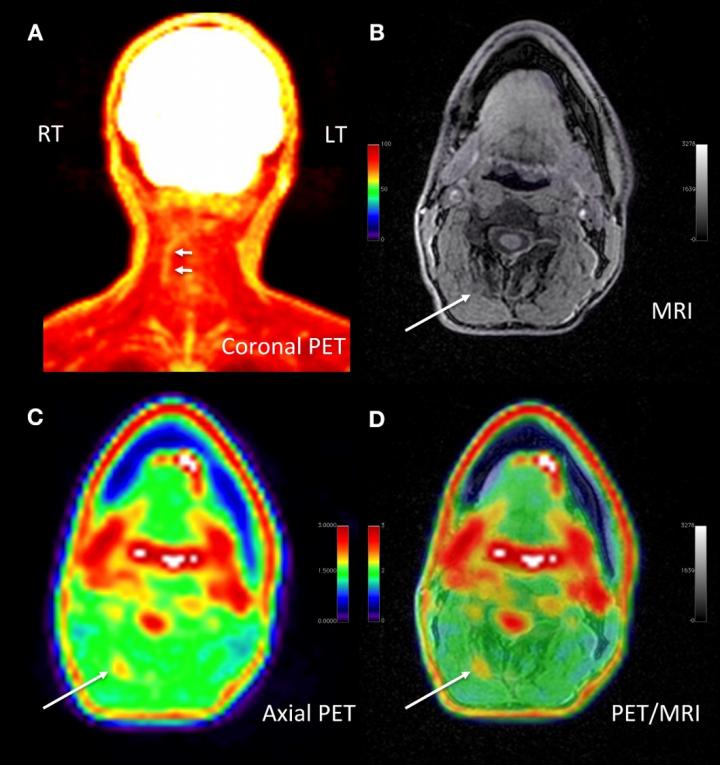

image: Adult male with decades of right neck pain, discomfort and tightening following birth injury. The patient had failed multiple standard therapeutic maneuvers before presenting for 18F-FDG PET/MR imaging. Images shows abnormally elevated FDG uptake (white arrows; SUVmax = 1.2) observed in a linear pattern in the space in the posterolateral right neck, between the oblique capitis inferior and the semispinalis capitis muscles, where the greater occipital nerve resides. By comparison, the same region on the contralateral, asymptomatic side of the neck has an SUVmax = 0.7. This result encouraged a surgeon to explore the area. The surgeon ultimately found a collection of small arteries wrapped around the nerve in this location. The small arteries underwent lysis by the surgeon and the patient reported tremendous relief of symptoms. (A) Coronal thick slab MIP of 18F-FDG PET. (B) Axial LAVA FLEX MRI through the cervical spine. (C) Axial PET at the same slice as the axial MRI. (D) Fused axial PET/MRI.

Cipriano, et al., Stanford University, CA.

A new molecular imaging approach utilizing 18F-FDG positron emission tomography (PET) and magnetic resonance imaging (MRI) can precisely identify the location of pain generators in chronic pain sufferers, often precipitating a new management plan for patients. This research was presented at the Society of Nuclear Medicine and Molecular Imaging 2020 Annual Meeting.

In the study, 65 chronic pain patients underwent 18F-FDG PET/MRI from head to foot. Maximum standardized uptake values and target-to-background ratios were measured using image analysis software. PET/MR images were evaluated by two radiologists to determine if increased 18F-FDG uptake occurred in the site of symptoms or in other areas of the body. Imaging results were then discussed with the referring physician, who determined whether a change in the pain management plan would follow.

Increased uptake of 18F-FDG in affected nerves and muscle was identified at the site of pain and other areas of the body in 58 out of 65 patients. This resulted in a mild modification of management plan (e.g., additional diagnostic test) for 16 patients and a significant modification for 36 patients (e.g., new invasive procedure suggested or ordered). In total, new management plans were implemented for 40 out of 65 patients, which had not been anticipated by the referring physician.